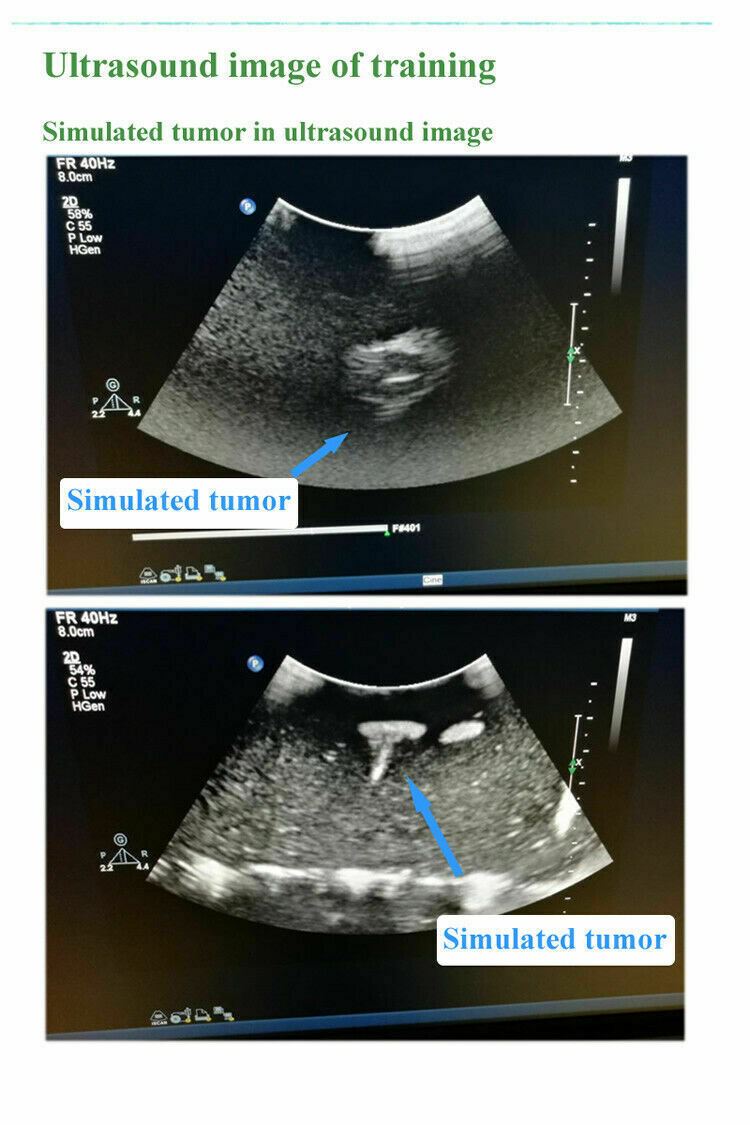

- A training teaching model for interventional Ultrasound

- Can be used for fine needle aspiration training

- Several different sized simulated high echo towers with the model